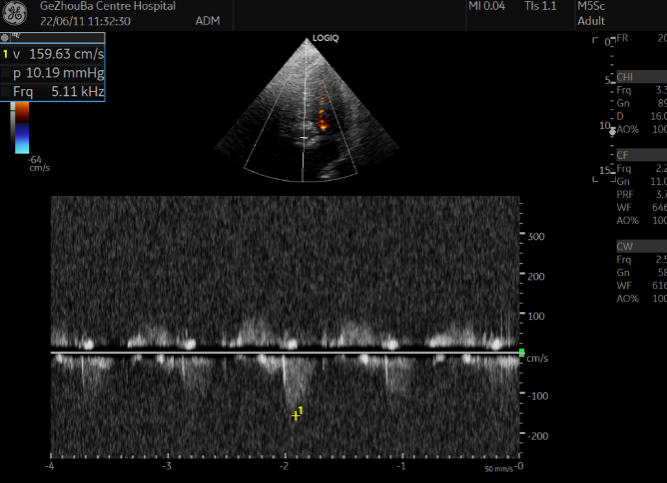

超声术后评估

超声显示最大流速降到1.59m/s,峰值压差10.19mmHg,假体瓣膜形态良好,工作正常,左右融合钙化嵴处存在少量瓣周漏。

术后超声评估